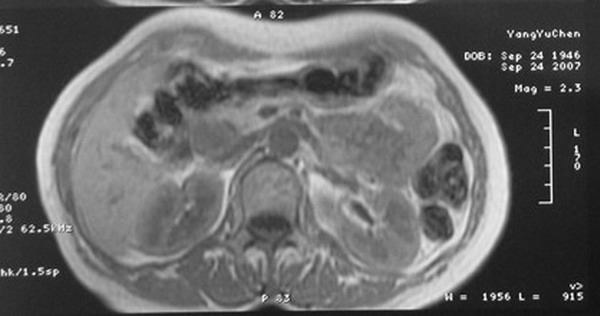

标题: MRI2066:腹膜后占位,请会诊,CT18531近期扫描图像

无明显不适,体检发现,

mri基本排除血管类肿瘤,明显强化说明极富血供,临床无症状,考虑胰岛细胞瘤可能大。

强化明显,并见有血管与之相连;考虑巨淋巴增生症.

极富血供的占位性病变,首先考虑良性,期待结果。